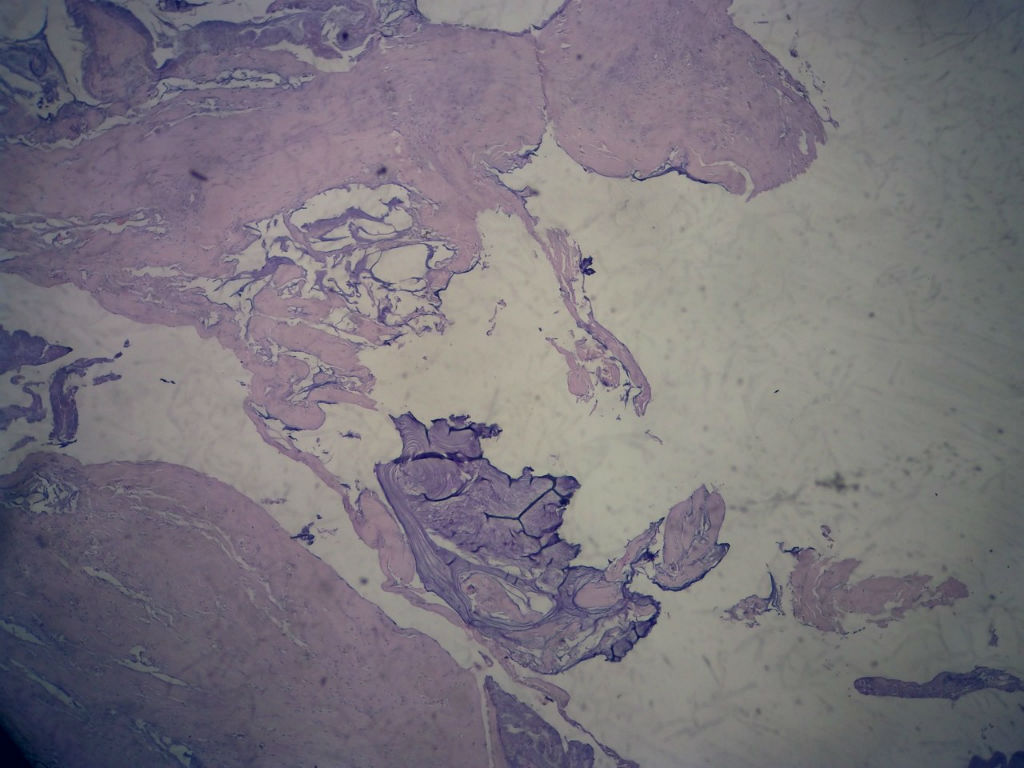

• 女,80岁,阑尾区肿块。图2

图2

送检为不规则组织多块,粘滑,解剖结构辨认不清。术中探查双侧卵巢无异常。

阑尾粘液性肿瘤,癌的可能性大

粘液长在肌层,而且漂浮着可疑上皮细胞,最大可能粘液腺癌。